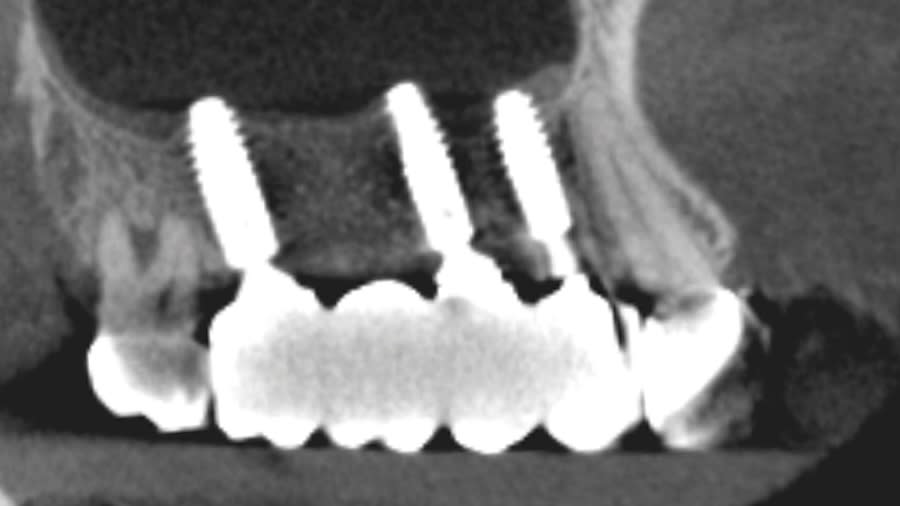

Case 1 (Figure 3 through Figure 24) depicts a 3-year follow-up of combined osseodensification sinus protocol IV in a severely resorbed maxillary ridge with ≤0.5 mm bone height in molar sites and horizontal deficiency at the first premolar site, using a two-stage approach for implant placement.

Case 2 (Figure 25 through Figure 36) illustrates a 3-year follow-up of the osseodensification sinus protocol IV in a severely resorbed right maxillary ridge with <0.5 mm bone height in molar sites, using a two-stage approach for implant placement.

Case 3 (Figure 37 through 44) shows a case of significant trauma history with a 3-year follow-up of the osseodensification sinus protocol IV in a severely resorbed right maxillary ridge with ≤0.5 mm bone height in molar sites, using a two-stage approach for implant placement.